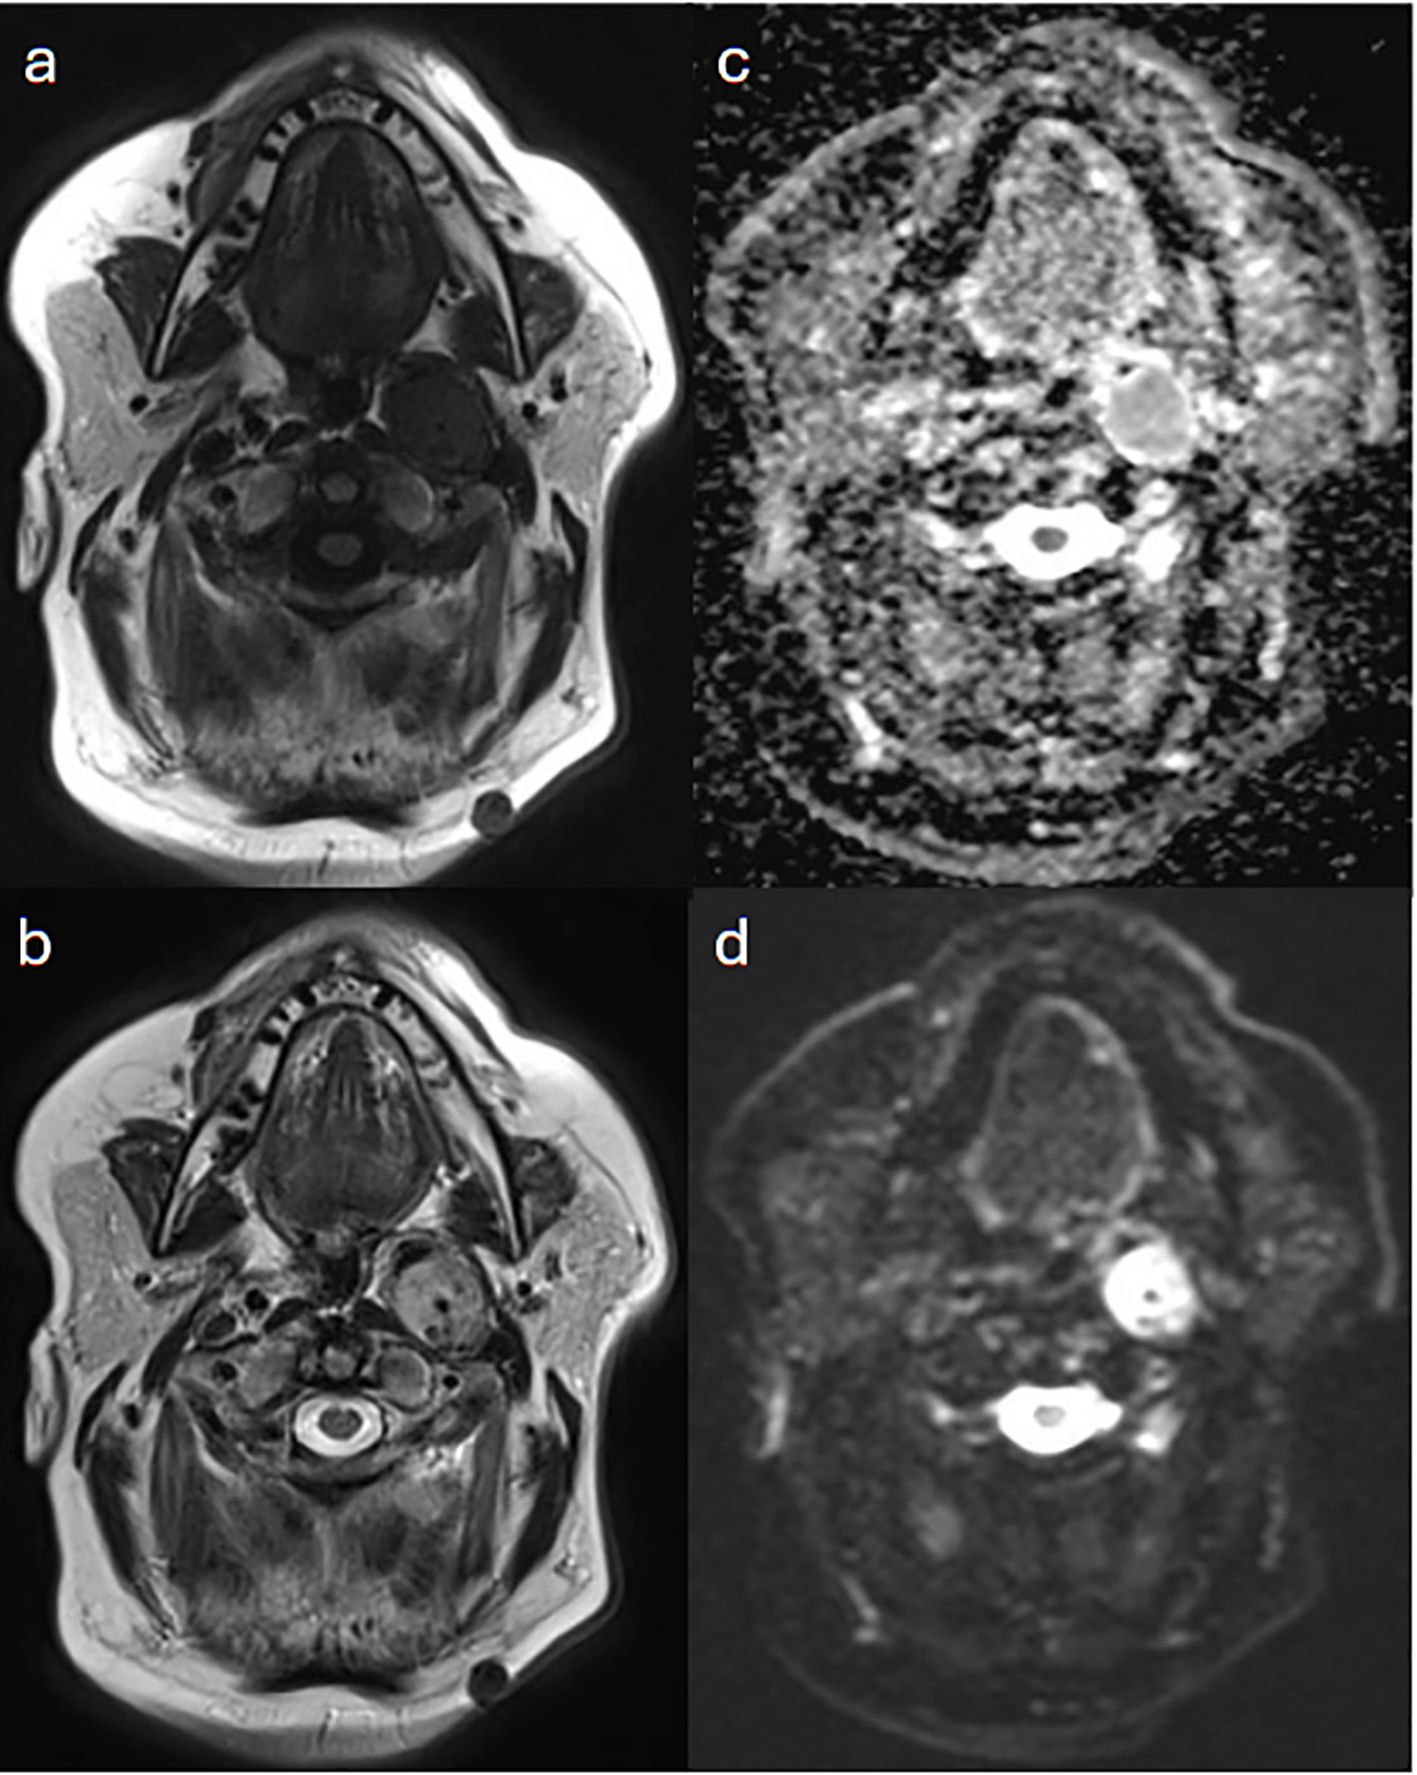

Background: Head and neck paragangliomas (HNPGs) are rare neuroendocrine tumors originating from neural crest cells, with some exhibiting malignant potential. Traditional imaging modalities, such as magnetic resonance imaging (MRI), often have limitations in detecting multifocal or metastatic disease, driving interest in more sensitive diagnostic approaches like Gallium-68 DOTATATE positron emission tomography/computed tomography (Ga-68 DOTATATE PET/CT). Methods: This retrospective study aimed to assess the effectiveness of Ga-68 DOTATATE PET/CT in the detection and management of HNPGs. Imaging data from 2015 to 2024 were reviewed, identifying four confirmed cases of HNPG. All patients underwent head and neck MRI and Ga-68 DOTATATE PET/CT scans. Data on imaging findings, treatment history, and clinical outcomes were collected and analyzed to compare the performance of Ga-68 DOTATATE PET/CT with other imaging techniques, including Iodine-123 meta-iodobenzylguanidine (I-123 MIBG) scintigraphy and Fluorine-18 fluorodeoxyglucose (F-18 FDG) PET/CT. Results: Ga-68 DOTATATE PET/CT demonstrated enhanced sensitivity in detecting both primary and metastatic lesions compared to MRI and other imaging modalities. It identified additional lesions not seen on MRI, confirmed local recurrence, and detected unsuspected metastatic sites, influencing clinical management. While Ga-68 DOTATATE PET/CT provided more diagnostic clarity than I-123 MIBG in one case, it also revealed additional metastatic sites in a patient with a succinate dehydrogenase (SDH) gene mutation, which were not detected by F-18 FDG PET/CT. Conclusion: Ga-68 DOTATATE PET/CT is a valuable imaging tool for evaluating HNPGs, with superior sensitivity in detecting both primary and metastatic lesions compared to conventional imaging. Its diagnostic advantages can significantly impact treatment planning and patient management. Integrating Ga-68 DOTATATE PET/CT into clinical guidelines for HNPG evaluation may enhance diagnostic accuracy. Further research with larger cohorts is warranted to confirm these findings and establish standardized interpretation criteria.